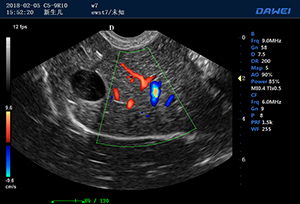

·支持B、C、PW、CW、寬景成像